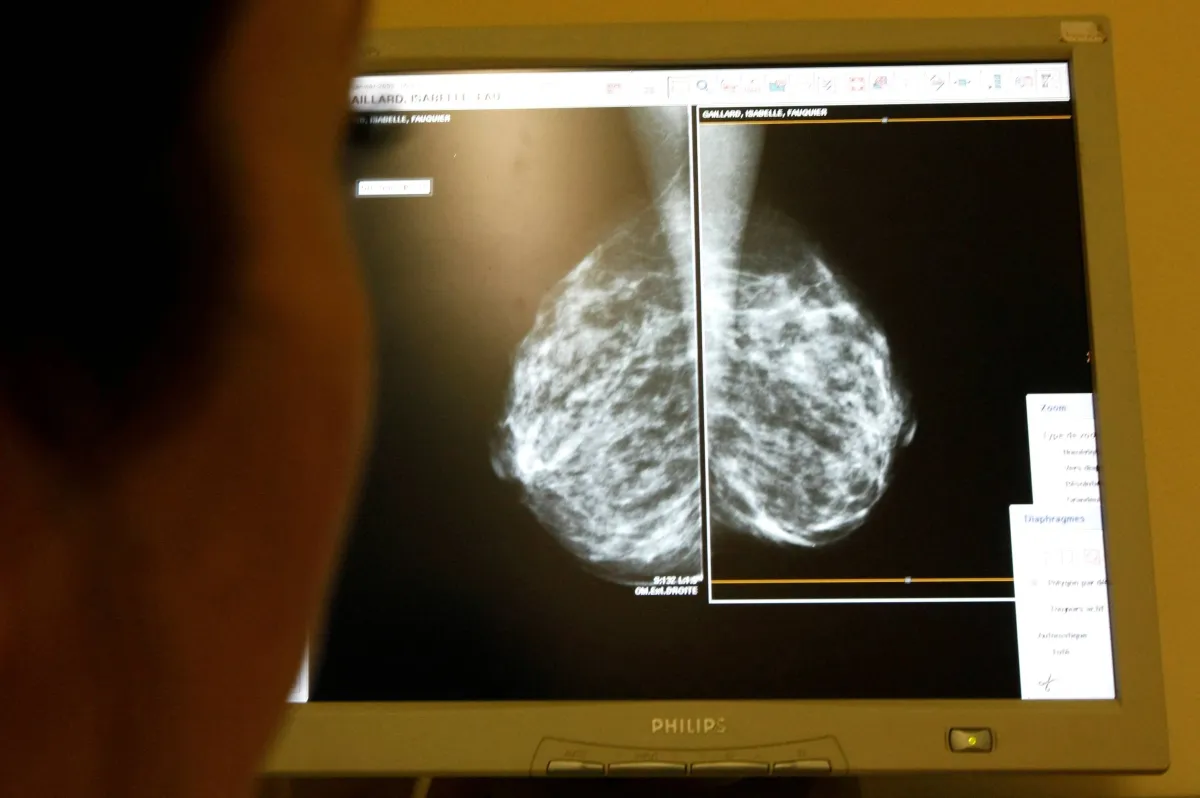

كشف باحثون بمركز لومباردي الشامل للسرطان بجامعة جورج تاون بالتعاون مع علماء بجامعة ميامي بفلوريدا عن عقار تجريبي جديد أطلق عليه TTP488 (azeliragon) يضعف سرطان الثدي العدواني الثلاثي السلبي الناتج عن انتشار النقائل على المستوى الخلوي.

ونشر الاكتشاف الجديد يوم (الخميس) الماضي بمجلة Nature Breast Cancer. وتمثل سرطانات الثدي ثلاثية السلبية (TNBCs) حوالى 10-15 % من جميع حالات سرطان الثدي المشخصة؛ وتتكون من خلايا سرطانية لا تحتوي على مستقبلات هرمون الاستروجين أو البروجسترون، ولا تنتج بروتينًا يسمى «HER2» بكميات كبيرة. فيما تعتبر TNBC أكثر شيوعًا عند النساء الأصغر من 40 عامًا أو النساء السوداوات؛ بالنسبة لتلك السرطانات التي تنتشر، فإن معدل البقاء على قيد الحياة لمدة خمس سنوات هو 12 % فقط.

ولقد استعصت TNBCs على العلاج الفعال لعقود. اما هذا الاكتشاف فهو يحدد بعض مسارات الإشارات والآليات الخلوية التي ينظم من خلالها مستقبل موجود على سطح خلايا TNBC يسمى مستقبل المنتجات النهائية للجليكشن المتقدم (RAGE) انتشاره القاتل. مسلحين بهذه المعرفة.

من أجل ذلك، تمكن الباحثون من اختبار فعالية TTP488 في كل من المختبر والفئران لإظهار أن الدواء يمكن أن يكون مفيدًا للمرضى.

ومن أجل المزيد من التوضيح، قال الدكتور باري هودسون الأستاذ المشارك بعلم الأورام بجامعة جورج تاون لومباردي المؤلف المقابل لهذا المقال «إن التجربة السريرية التي تجري الآن في لومباردي ومراكز السرطان الأخرى هي نتيجة مباشرة لهذا البحث قبل السريري حول مثبطات RAGE الذي بدأ بجامعة ميامي واستمر مع انتقالي إلى لومباردي». مضيفا أن «دراستنا هي الأولى التي تظهر أن TTP488 يضعف ورما خبيثا لسرطان الثدي في الخلايا والقوارض. إذ إنه مثبط RAGE الوحيد المعتمد للاستخدام في البشر، وبالتالي فإن الآثار المترتبة على التجارب السريرية عديدة». وذلك وفق ما نشر موقع «ميديكال إكسبريس» الطبي المتخصص.

وتم اكتشاف RAGE عام 1992 كعامل محتمل له دور في مضاعفات الأوعية الدموية لمرض السكري. وقد ثبت لاحقًا أنه متورط في مجموعة واسعة من الأمراض بسبب قدرته الشائنة على ربط العديد من الجزيئات المختلفة والحث على الالتهاب. وبناءً على هذه المعرفة، تم تطوير TTP488 عام 2000 لعلاج مرض ألزهايمر، لكن نتائج التجارب على الدواء كانت ملتبسة. ومع ذلك، فاستنادا لمعرفة أحدث حول علم الأحياء وتأثيراته، بما في ذلك توافره على نطاق واسع عبر العديد من الأنظمة البيولوجية وملف تعريف الأمان المشجع، يبدو الآن أنه مرشح واعد جدًا للتجارب السريرية.

وفي هذا الاطار، بدأ الباحثون دراستهم من خلال النظر في اثنين من مثبطات RAGE: TTP488 و FPS-ZM1، وكلاهما يضعف ورما خبيثا عفويا وتجريبيا لـ TNBC في الفئران. لكن بعد دراسة مستفيضة في المختبر وفي الفئران، كان من الواضح أن عقار TTP488 هو الدواء الأكثر فاعلية الذي اتبعوه على نطاق واسع بما يكفي لمعرفة ما إذا كان مؤهلًا للاستخدام في الأشخاص بالتجارب السريرية. بينما لا يزال TTP488 بحاجة إلى الاختبار بتجارب سريرية أكبر وأكثر تقدمًا لإثبات فعاليته الحقيقية. من أجل ذلك، هو غير متاح بعد للنساء غير المسجلات في التجارب السريرية.

وحدد المحققون أيضًا ثلاثة مسارات مهمة يمكن أن تؤدي إلى تثبيط RAGE: Pyk2 و STAT3 و Akt. إذ سيساعد هذا الاكتشاف الباحثين على فهم الآليات التي يقود بها RAGE النقائل، ومن المحتمل أن تتمكن المنظومة العلاجية المركبة من استهداف RAGE وهذه المسارات.

ويخلص هدسون الى القول «نحن نختبر حاليًا توليفات مختلفة من TTP488 مع علاجات أخرى مضادة للسرطان لتحديد ما إذا كانت مثبطات RAGE يمكنها التآزر مع تلك العلاجات». مرجحا «أعتقد أن النظرة إلى العلاج الفعال لسرطانات الثدي ثلاثية السلبية أصبحت أكثر إشراقًا في الآونة الأخيرة».